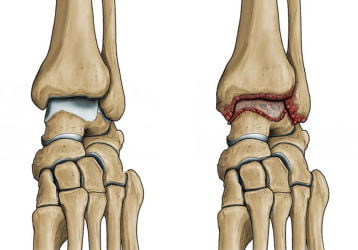

Симптомы и лечение деформирующего артроза голеностопного сустава

Особенности деформирующего характера артроза голеностопа. Перспективы полного излечения в зависимости от степени заболевания.